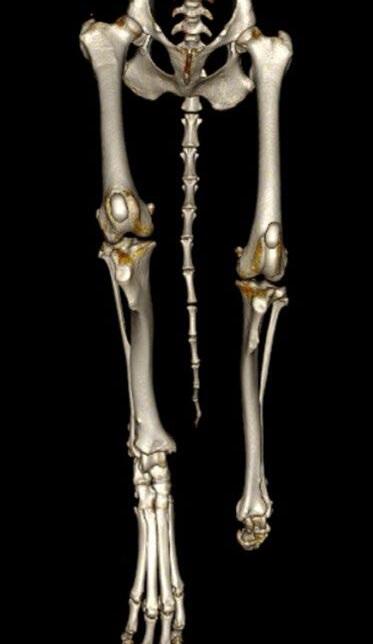

Osseointegrated Transcutaneous Amputation Prostheses in Veterinary Medicine

Daniel R James